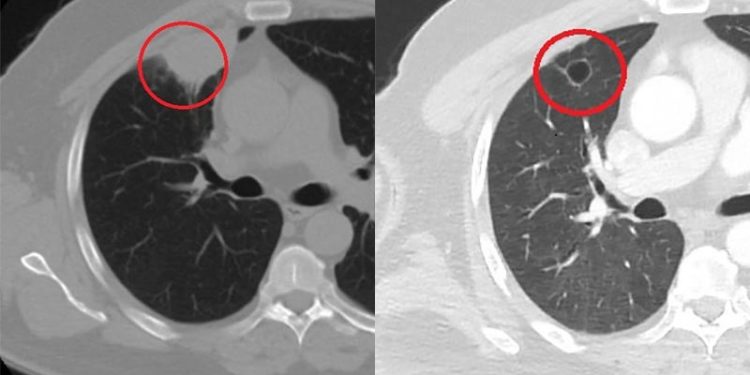

Ameliyat öncesi N.T.’nin Covid-19 testi pozitif çıkınca operasyon ertelendi. Koronavirüs tedavisine başlanan N.T.’nin son testi negatif çıktı. Dr. Fatoş Kozanlı, tedavi sonrası tomografisi çekilen N.T.’nin akciğerindeki tümörün yok olduğunu gördü. Kozanlı, N.T.’nin kendilerine başvurduğunda koronavirüs belirtisi olmadığını ancak ameliyat öncesi PCR testi yaptıklarını söyledi. Koronavirüs tedavisinin ardından ortaya çıkan sonucun kendisini de şaşırttığını belirten Kozanlı, şunları söyledi:

“Hastamız, çalıştığı başka bir kentte göğsünden darbe alıyor ve ağrıları geçmeyince bir üniversite hastanesine başvuruyor. Burada hastaya bir akciğer grafisi çekiliyor. Sağ akciğerinde bir kitleye rastlanıyor. Daha sonra hastaya, bir akciğer tomografisi çekiliyor ve göğüs cerrahisi için önemli büyüklükte olan 4 santimetre çapında, akciğer kanserine benzer özellikte radyolojik bulgular olan bir kitle tespit ediliyor. Daha sonra hastaya yapılan ileri tetkiklerde akciğer kanseri teşhisi konuluyor. Hastaya bir cerrahi planlanıyor. Hasta Kahramanmaraşlı olduğu için kendi memleketine gelmeyi tercih ediyor. Bize başvurdu ve göğüs ağrısı şikayeti vardı. Öksürük, nefes darlığı, balgam çıkarma, ateş gibi şikayetleri yoktu. Hastayı biz de değerlendirdik ve ameliyat olmasına karar verdik. Çünkü akciğer kanserine çok benzer radyolojik bulguları vardı. Sağlık Bakanlığımızın kuralları gereği her hastayı ameliyat öncesi PCR testi yapılır. Biz de ameliyat gecesi hastadan PCR testi aldık ve testi pozitif geldi. Ameliyatımızı 14 gün erteledik ve hastamıza koronavirüs tedavisi uygulandı. Hasta 14’üncü gün tekrar bize başvurdu ve yapılan PCR testi negatif çıktı. Yeni bir tomografi çektik ve tümörün tamamen ortadan kalktığını gördük. Şimdi sonuç bilgilerinden başlangıca gittiğimizde, bu bir akciğer kanseri olsaydı, ortadan kalkması mümkün değildi. Başka bir patolojiye bağlı durum olsaydı, yine verdiğimiz tedaviyle ortadan kalkmasını çok beklemeyiz. Antiviral tedavisi verdik ve hastanın radyolojik bulguları neredeyse tamamen normale döndü. Hastaya bunu izah ettik, ‘Dünya literatüründe hiç görülmeyen bir radyolojik bulgu’ diyerek. Bu gördüğümüz manzara artık hastanın akciğer grafisinde yok, akciğer kanseri değil. “

Hastayı takip etmeye devam ettiklerini belirten Kozanlı, 2 yıldır dünyayı etkisi altına alan koronavirüsün akciğer kanserini taklit ettiğini, böyle bir durumla ilk defa karşılaştıklarını söyledi. Hem Türkiye’de hem de diğer ülkelerde buna benzer bir vakanın olup olmadığını araştırdığını ifade eden Kozanlı, “Genel olarak dünya literatürüne baktığımızda koronavirüsün akciğer bulguları, radyolojik bulguları infiltrasyon, buzlu cam dansitesi gibi bilinen bulgular. Ama bizim hastamızda akciğer tümörünü taklit eden bir kitle vardı. Ve biz bunu dünya literatüründe hiç görmemiştik. Bununla ilgili geniş çaplı bir araştırma yaptım. Hem kendi deneyimlerimden hem kendi hastanemizde yatan hastalardan yola çıkarak birçok hastanın radyolojik bulgularına baktık. Dünya literatürlerini karıştırdım, diğer arkadaşlarıma danıştım, benzeri bulguya rastlamadım” diye konuştu. (DHA)